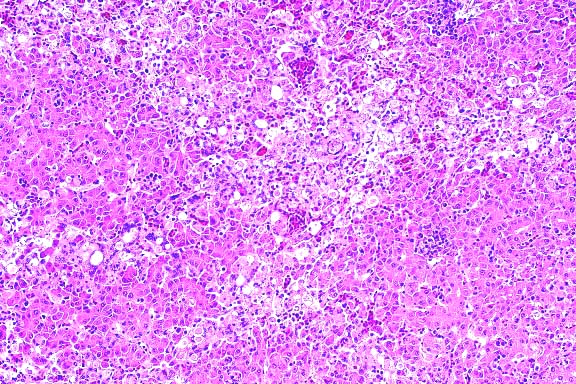

- Contributor's Diagnosis and Comments: Lung, pneumonia,

caseonecrotic, cavitating.

Etiology: Mycobacterium avium.

- Case 16-1. Lung. Central area of cavitary necrosis

is surrounded by congested, consolidated lung parenchyma.

- AFIP Diagnosis: Lung: Pneumonia, granulomatous and

necrotizing, diffuse, severe, with cavitation and mineralization,

Matschie's tree kangaroo (Dendrolagus matschiei), marsupial.

- In the group of diseased tree kangaroos studied by the contributor,

gross and microscopic lesions due to MAC infection have been

observed in several organ systems. However, the most extensive

lesions have occurred in the lungs and bones, and were histologically

characterized by necrotizing pyogranulomatous pneumonia and osteomyelitis

with numerous acid-fast bacilli. The Ziehl-Neelsen and Fite's

staining methods performed at the AFIP demonstrated acid-fast

bacilli in a section of lung from this tree kangaroo.